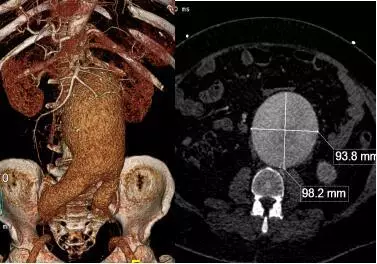

男性患者,66岁,以“腹痛3天”入院,查体:脐周可触及波动性包块,约8×10cm大小,压痛。

向家属简要讲明病情危重性及目前治疗方案的可选项(开放手术治疗及腔内“三明治”保留分支微创治疗),急症行腹主动脉瘤腔内修复+右髂内动脉栓塞+三明治重建左髂内动脉。术后患者动脉瘤完全隔绝,转危为安,如下面图片所示: